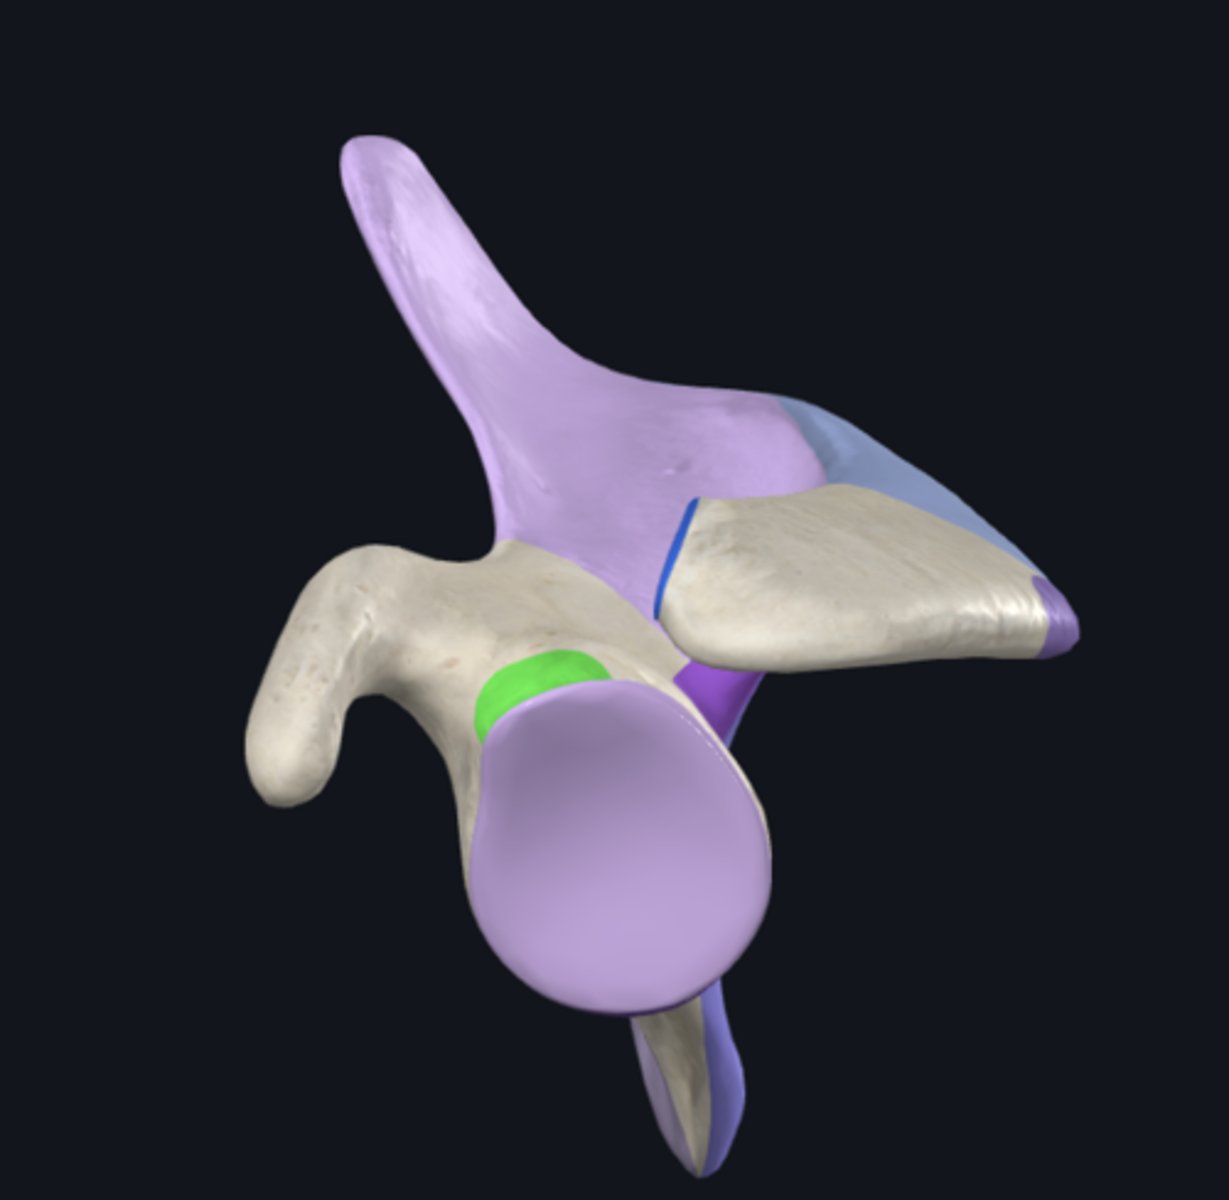

Acromion

Coracoid process

glenoid fossa

anatomical neck of humerus

greater tubercle

head of humerus

lesser tubercle

Crest of greater tubercle

crest of lesser tubercle

bicipital groove

surgical neck of humerus